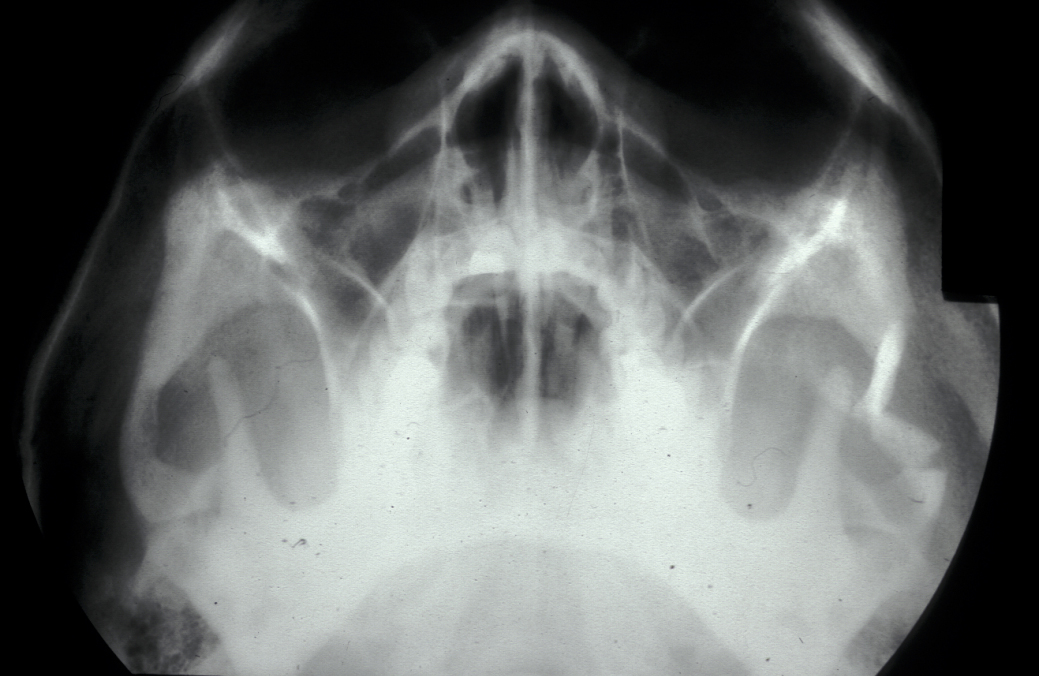

Plain film X-ray radiographs from different angles generally give sufficient diagnostic information. Combined they give good imaging of the zygomatic complex and can be used to determine the level of displacement and fracture pattern. Teardrop appearance into the maxillary antrum suggests an isolated orbital floor fracture (a 'blow out orbital fracture'; see Figure 8). Identification of this type of fracture mandates further investigation by a coronal (vertical plane view) CT scan and Hess chart test (eye test to assess motility of the eye).

Isolated zygomatic arch fractures are best visualised on a submentovertex view (view at base of skull). However, an adequate view of the fracture is usually visible on occipitomental views (see Figure 9).

Figure 9: Depressed fracture of the zygomatic arch causing trismus.